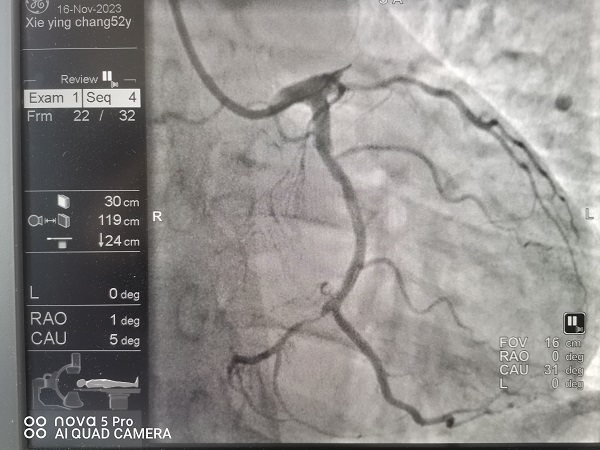

宜春学院第一附属医院 万载县人民医院心血管科涂小明主任正在总查房,突然收到胸痛中心远程会诊提示,原来是经过胸痛中心培训的黄茅镇卫生院医生首诊之后已完成了心电图检查并确诊了急性心肌梗死,然后发出了远程胸痛病人预警,涂小明主任根据心电图结果再次确诊后立即启动介入导管待命,09:30救护车进入我院大门后绕行我院急诊科及心血管科直达导管室,手术人员紧密合作,消毒、铺巾、穿刺桡动脉、造影、进指引导管、09:46过导丝,D2B(D2W)时间仅16分钟!创造了我院介入导管室抢救急性心肌梗死新的记录!

D2B(或D2W)时间是指急性心肌梗死病人进入医院大门到球囊(或导丝)通过病人冠状动脉血栓的时间,是胸痛中心质量控制反应急性心肌梗死救治水平最重要的的一个指标,90分钟之内达标,平均水平在60分钟左右。